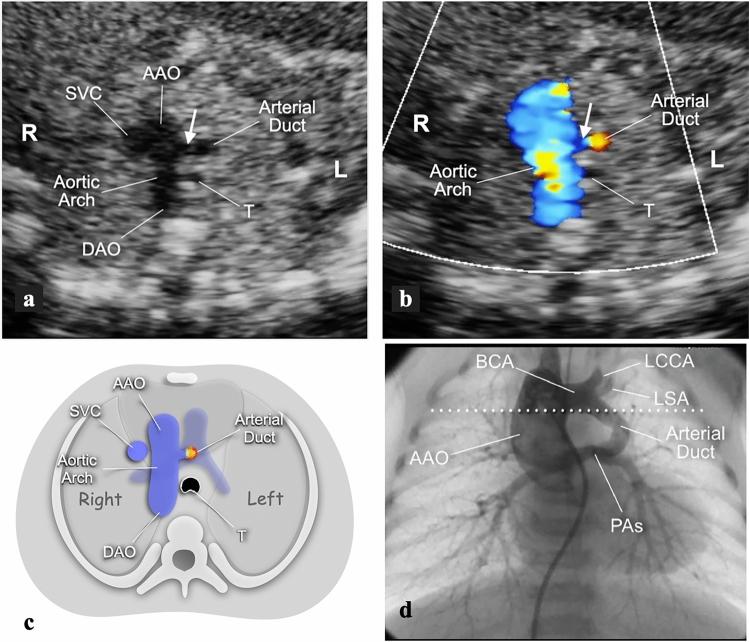

To study the different characteristics of arterial duct (AD) in a series of prenatally detected right aortic arch (RAA). Out of 832 congenital heart diseases (CHD) referred to a tertiary center, 98 cases had RAA. Based on anatomical landmarks we identified 7 types of AD: type 1 left-sided, transverse; type 2 left-sided, vertical; type 3 from the underside of aortic arch (AA), vertical; type 4 right-sided, mirror-image "V", transverse; type 5 right-sided, "H" shaped, transverse; type 6 bilateral; type 7 absent or unidentifiable. For each type of AD the incidence of associated major CHD was calculated and chi-square test was applied to verify the null hypothesis with significance level of p < 0.05. Type 1 occurred in 43% of cases including 4 with CHD and no cases with pulmonary outflow obstruction (POO). Symptoms of vascular ring were present in 41% of survivors. Type 2, 3 and 7 AD were associated with tetralogy of Fallot (TOF) or equivalents. No type 5 AD with CHD had POO and 3 isolated cases had asymptomatic hypoplasia of left pulmonary artery (LPA). Two type 6 AD had disconnection of LPA. Type 1 occurred more often as an isolated finding (p < 0.001), whereas types 2 (p = 0.0026), 3 (p = 0.0045), 4 (p = 0.0325) and 7 (p = 0.0001) were frequently associated with major CHD. In RAA, type 1 (U-shaped) is usually an isolated finding (p < 0.001) which includes all symptomatic vascular rings. POO is always present when the AD is vertical or absent but not when it lies on a transverse plane. Bilateral AD is rare and brings the risk of functionary loss of left lung if not identified.

研究一系列产前检测到的右主动脉弓(RAA)中动脉导管(AD)的不同特征。在转诊至三级中心的 832 例先天性心脏病(CHD)中,有 98 例存在 RAA。根据解剖学标志,我们确定了 7 种类型的 AD:1 型为左侧、横向;2 型为左侧、垂直;3 型为主动脉弓(AA)底部、垂直;4 型为右侧、镜像“V”形、横向;5 型为右侧、“H”形、横向;6 型为双侧;7 型为缺失或无法识别。对于每种类型的 AD,计算了相关主要 CHD 的发生率,并应用卡方检验来验证具有统计学意义的 p<0.05 的零假设。1 型发生在 43%的病例中,包括 4 例 CHD 患者和无肺流出道梗阻(POO)的患者。41%的幸存者存在血管环症状。2、3 和 7 型 AD 与法洛四联症(TOF)或等效物相关。无 CHD 的 5 型 AD 伴有 POO,3 例孤立性左肺动脉(LPA)发育不全。2 例 6 型 AD 存在 LPA 分离。1 型更常作为孤立性发现(p<0.001),而 2 型(p=0.0026)、3 型(p=0.0045)、4 型(p=0.0325)和 7 型(p=0.0001)常与主要 CHD 相关。在 RAA 中,1 型(U 形)通常为孤立性发现(p<0.001),包括所有有症状的血管环。当 AD 垂直或缺失时,POO 总是存在,但当 AD 位于横平面时则不存在。双侧 AD 罕见,如果未识别,会导致左肺功能丧失。